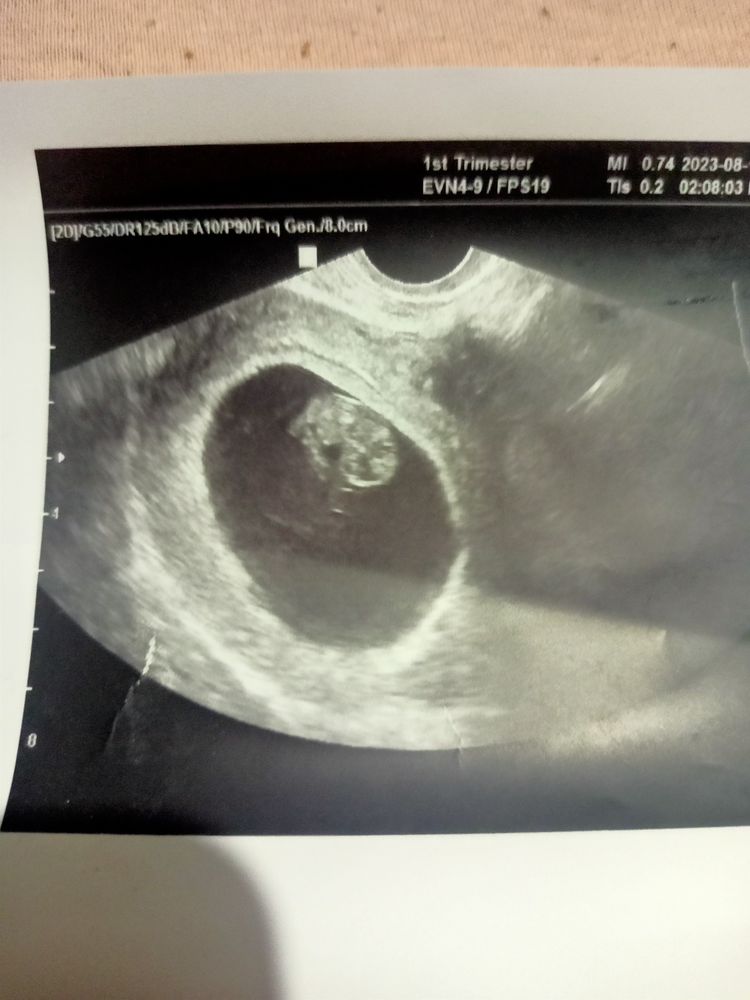

Марина Монако, тут на фото 7 недель 6 дней

Срок 11.3,тоже большое ПЯ